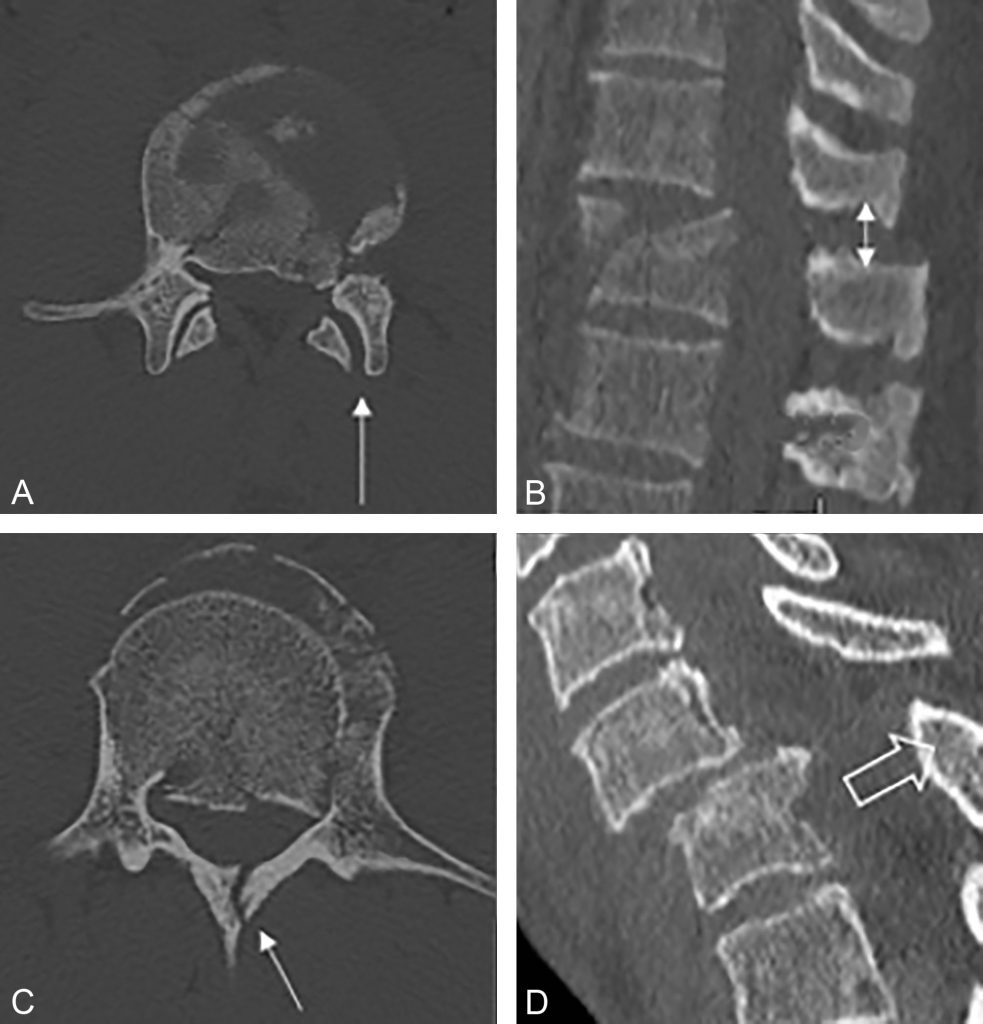

On recherche des signes de lésion du complexe ligamentaire postérieur en scanner, prédictifs d’instabilité (figure 86.2) :

- augmentation de la distance inter-facettaire ;

- augmentation de la distance inter-épineuse (> 7 mm) ;

- augmentation de 2 mm de l’espace inter-lamaire ;

- fracture du processus épineux ;

- subluxation du corps vertébral de plus de 2 mm par rapport aux vertèbres adjacentes.

Fig. 86.2 Scanner montrant des signes indirects de lésions du complexe ligamentaire postérieur : diastasis articulaire postérieur (A), diastasis inter-épineux (B), fracture du processus épineux (C), subluxation du corps vertébral de plus de 2 mm (D).

Source : CERF, CNEBMN, 2022.